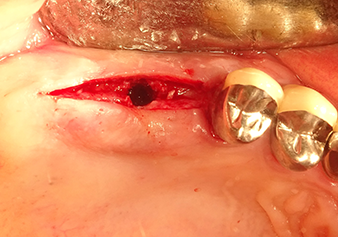

A 49-year-old female patient, a non-smoker and with nothing remarkable in her general medical history, was referred to our oral surgery practice for surgical extraction of tooth 16 and subsequent implantation. After the extraction, the patient experienced mild sinusitis trouble with the resultthat we initially waited six months before carrying out the measure. The residual bone height at the planned implant position measured 3-4 mm (Fig. 1 and 2).

Following atraumatic preparation of the mucoperiosteal flap, the implant position was marked with the I1 instrument and the site prepared – until initial resistance was felt. Piezosurgical instruments were used in an up and down movement without any pressure being exerted. The piezoelectric vibration produced the desired and efficient cavitation.

The I2A instrument (diameter 2.0 mm) was then used to perforate the sinus floor intermittently and on the smallest scale possible. This special piezosurgical method ensures that the Schneiderian membrane is not damaged. When the Z25P was used, the membrane was already lifted slightly by the coolant supplied via the instrument tip (Fig. 3). The coolant quantity was just 50% in order to avoid high pressure in the implant bed.